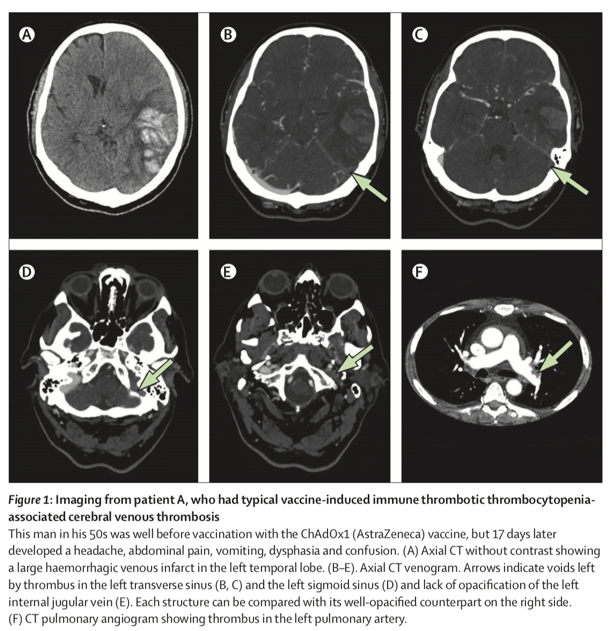

该研究首次表明 , VITT相关脑静脉血栓形成患者与非VITT患者相比 , VITT相关的患者更年轻 , 并且更可能接种过阿斯利康的(ChAdOx1)疫苗 。 此外 , 其中有更大比例的颅内静脉血栓(intracranial veins thrombosed)和颅外血栓(extracranial thrombosis) , 且患者中死亡和需依靠他人照料的比例更大 。

研究发现 , 在疫苗诱发免疫血栓性血小板减少(VITT)情况下 , 脑静脉血栓形成(CVT)情况更为严重 。 在接种疫苗后未患有VITT的脑静脉血栓形成患者中 , 大约有16%的患者死亡或需依赖他人照料日常生活 , 这一比例在VITT相关的脑静脉血栓形成患者中为47% , 是前者的3倍多 。

2021年4月至5月20日期间 , 研究者从英国43家医院共收集95名接种新冠疫苗后出现脑静脉血栓形成病例的有效数据 , 其中70人患有VITT , 25人未患VITT 。 研究者详细记录了VITT相关的脑静脉血栓形成患者的临床特征、实验室和影像学结果 , 并将其与未患VITT的脑静脉血栓形成患者以及国际脑静脉和硬膜窦血栓研究(International Study on Cerebral Venous Vein and Dural Sinus Thrombosis, ISCVT)队列的624名患者的历史数据进行比较 。

研究表明 , VITT相关的脑静脉血栓形成病例明显比非VITT病例年轻(见表1) 。 研究对70名VITT相关脑静脉血栓形成患者与25例接种疫苗的非VITT脑静脉血栓形成患者进行比较 。 70例VITT相关病例都发生在第一剂阿斯利康疫苗后;25名非VITT病例中 , 21例(85%)发生在接种第一剂阿斯利康疫苗后 , 其余4例在第一剂(3例)或第二剂(1例)辉瑞疫苗后发生 。